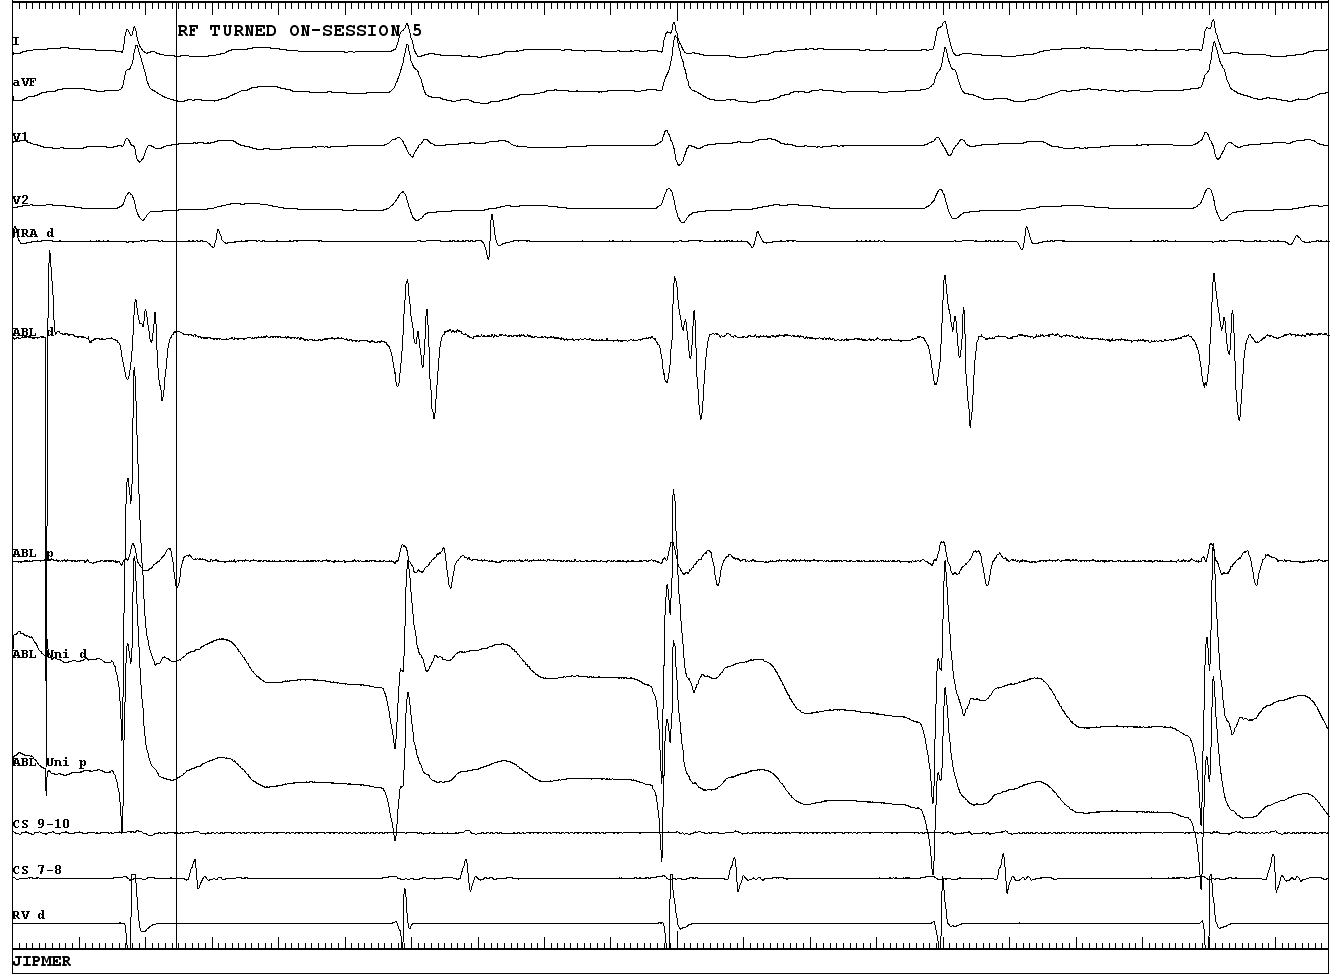

EGM setup

map_signals.jpg

EGM set up

egm_setup.JPG

Unipolar

unipolar_good.JPG

EGM target

Earliest A or shortest VA ?

earliest_a.jpg